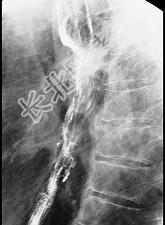

- 单项选择题女性患者,67岁进行性吞咽困难半年, X线及CT检查如图,应诊断为 ( )

A、食管癌

B、食管憩室

C、食管炎

D、食管良性狭窄

E、食管静脉曲张